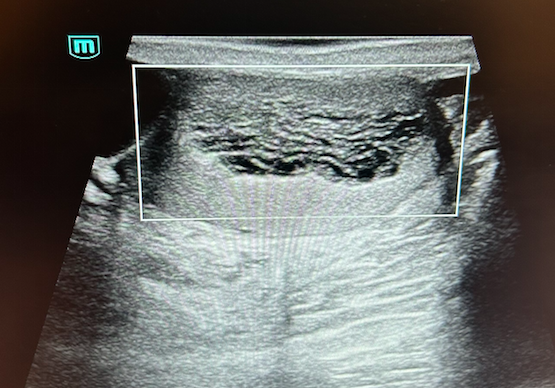

Teste derecho con imagen anecoica de bordes bien definidos y doppler negativo sugerente de quiste en polo superior de 33 x 55 mm. En teste izquierdo imagen anecoica en polo superior de bordes bien definidos y Doppler negativo, de 3 cm de diámetro,sugerente de quiste. Llama la atención adyacente a quiste, imagen en parénquima testicular, de patrón heterogéneo que ocupa el 50% con doppler negativo.